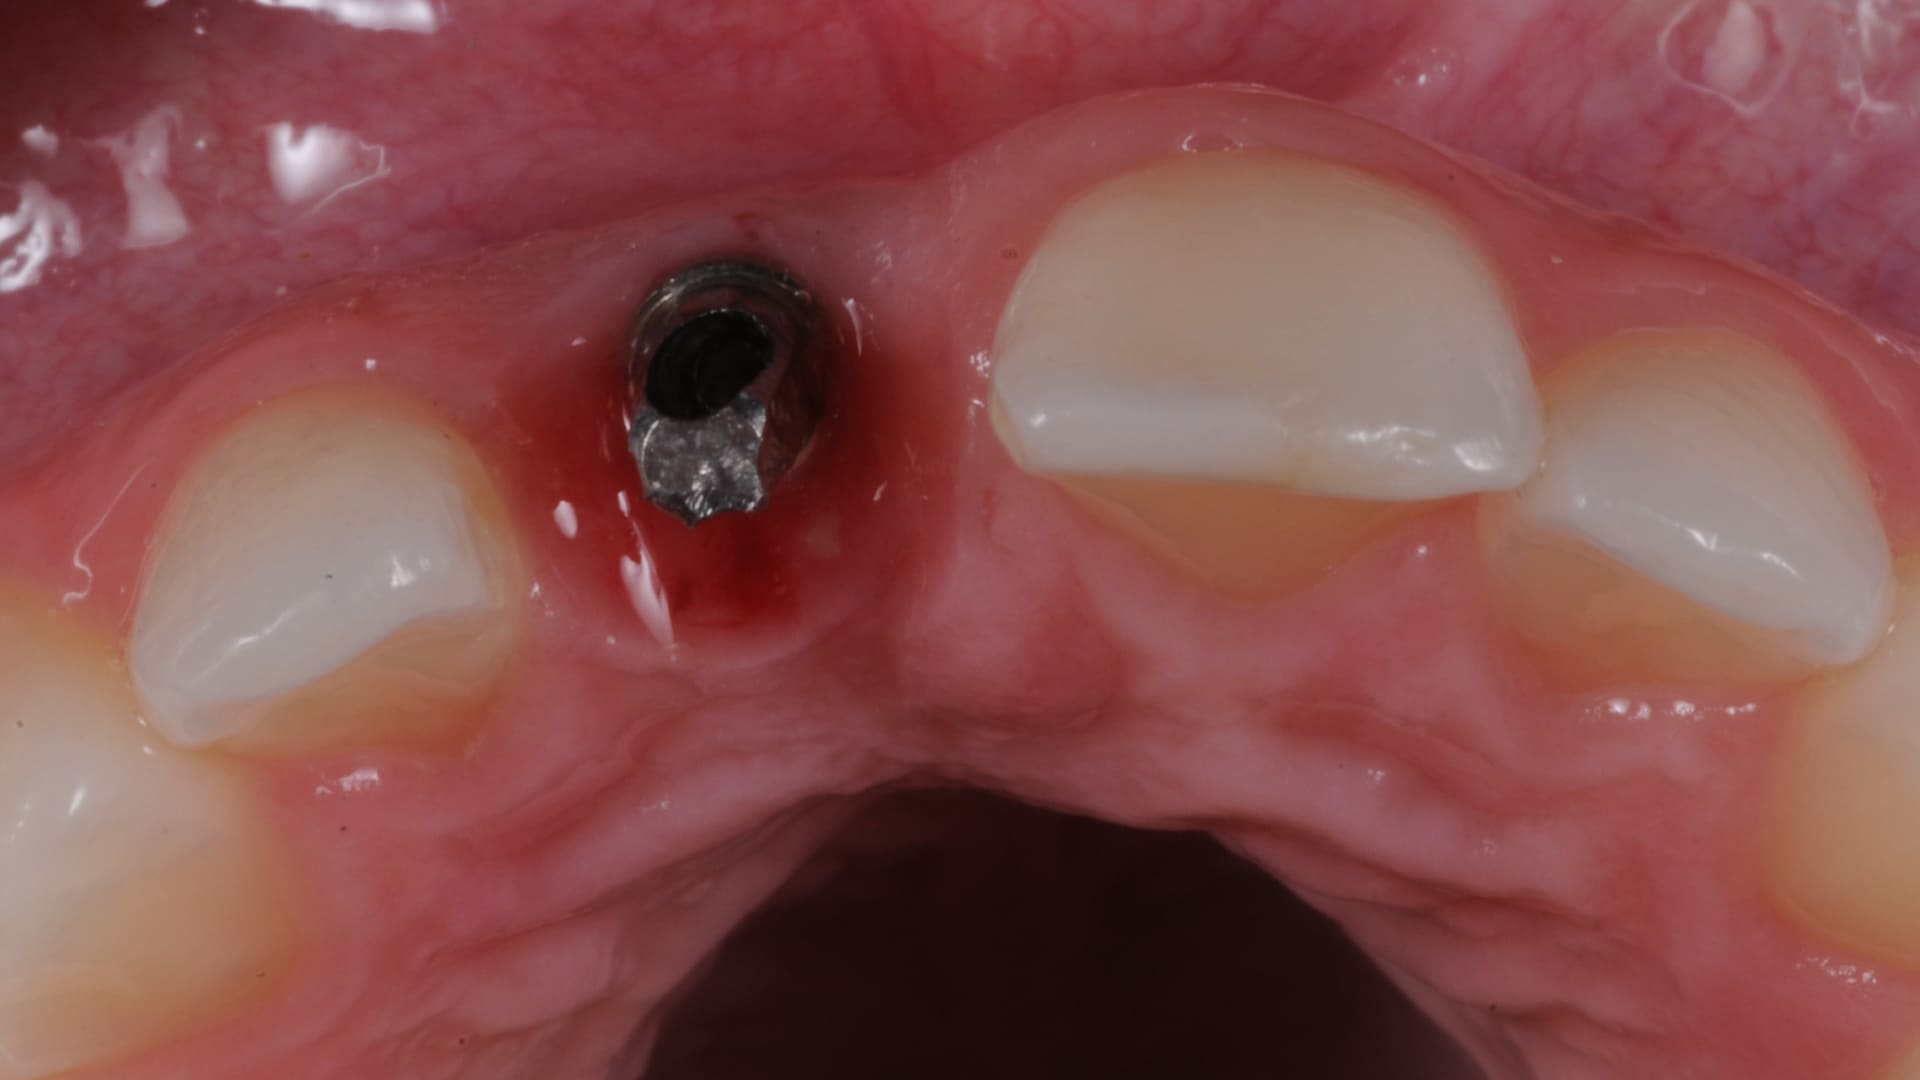

Customized Healing abutments:

how to do it.

Customized healing in the posterior sites